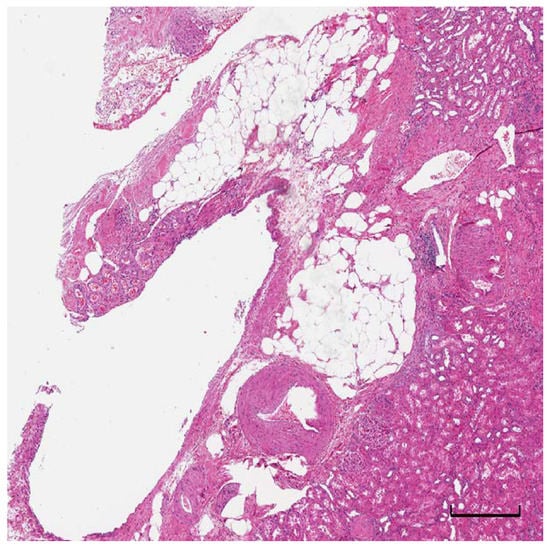

4. Pathological Assessment and Prognostic Value of Adipose Tissue in RCC

- Cimadamore, A.; Palagonia, E.; Piccinni, P.; Misericordia, M.; Galosi, A.B.; Montironi, R. Inguinal bladder hernia with lipomatosis of the bladder wall: A potential clinical pitfall for cancer. Urologia 2019, 86, 35–38. [Google Scholar] [CrossRef]

- Wahal, S.P.; Mardi, K. Idiopathic renal replacement lipomatosis: A rare renal pseudo tumor. J. Cancer Res. Ther. 2014, 10, 428–430. [Google Scholar] [CrossRef]

- Bonsib, S.M. The renal sinus is the principal invasive pathway: A prospective study of 100 renal cell carcinomas. Am. J. Surg. Pathol. 2004, 28, 1594–1600. [Google Scholar] [CrossRef]